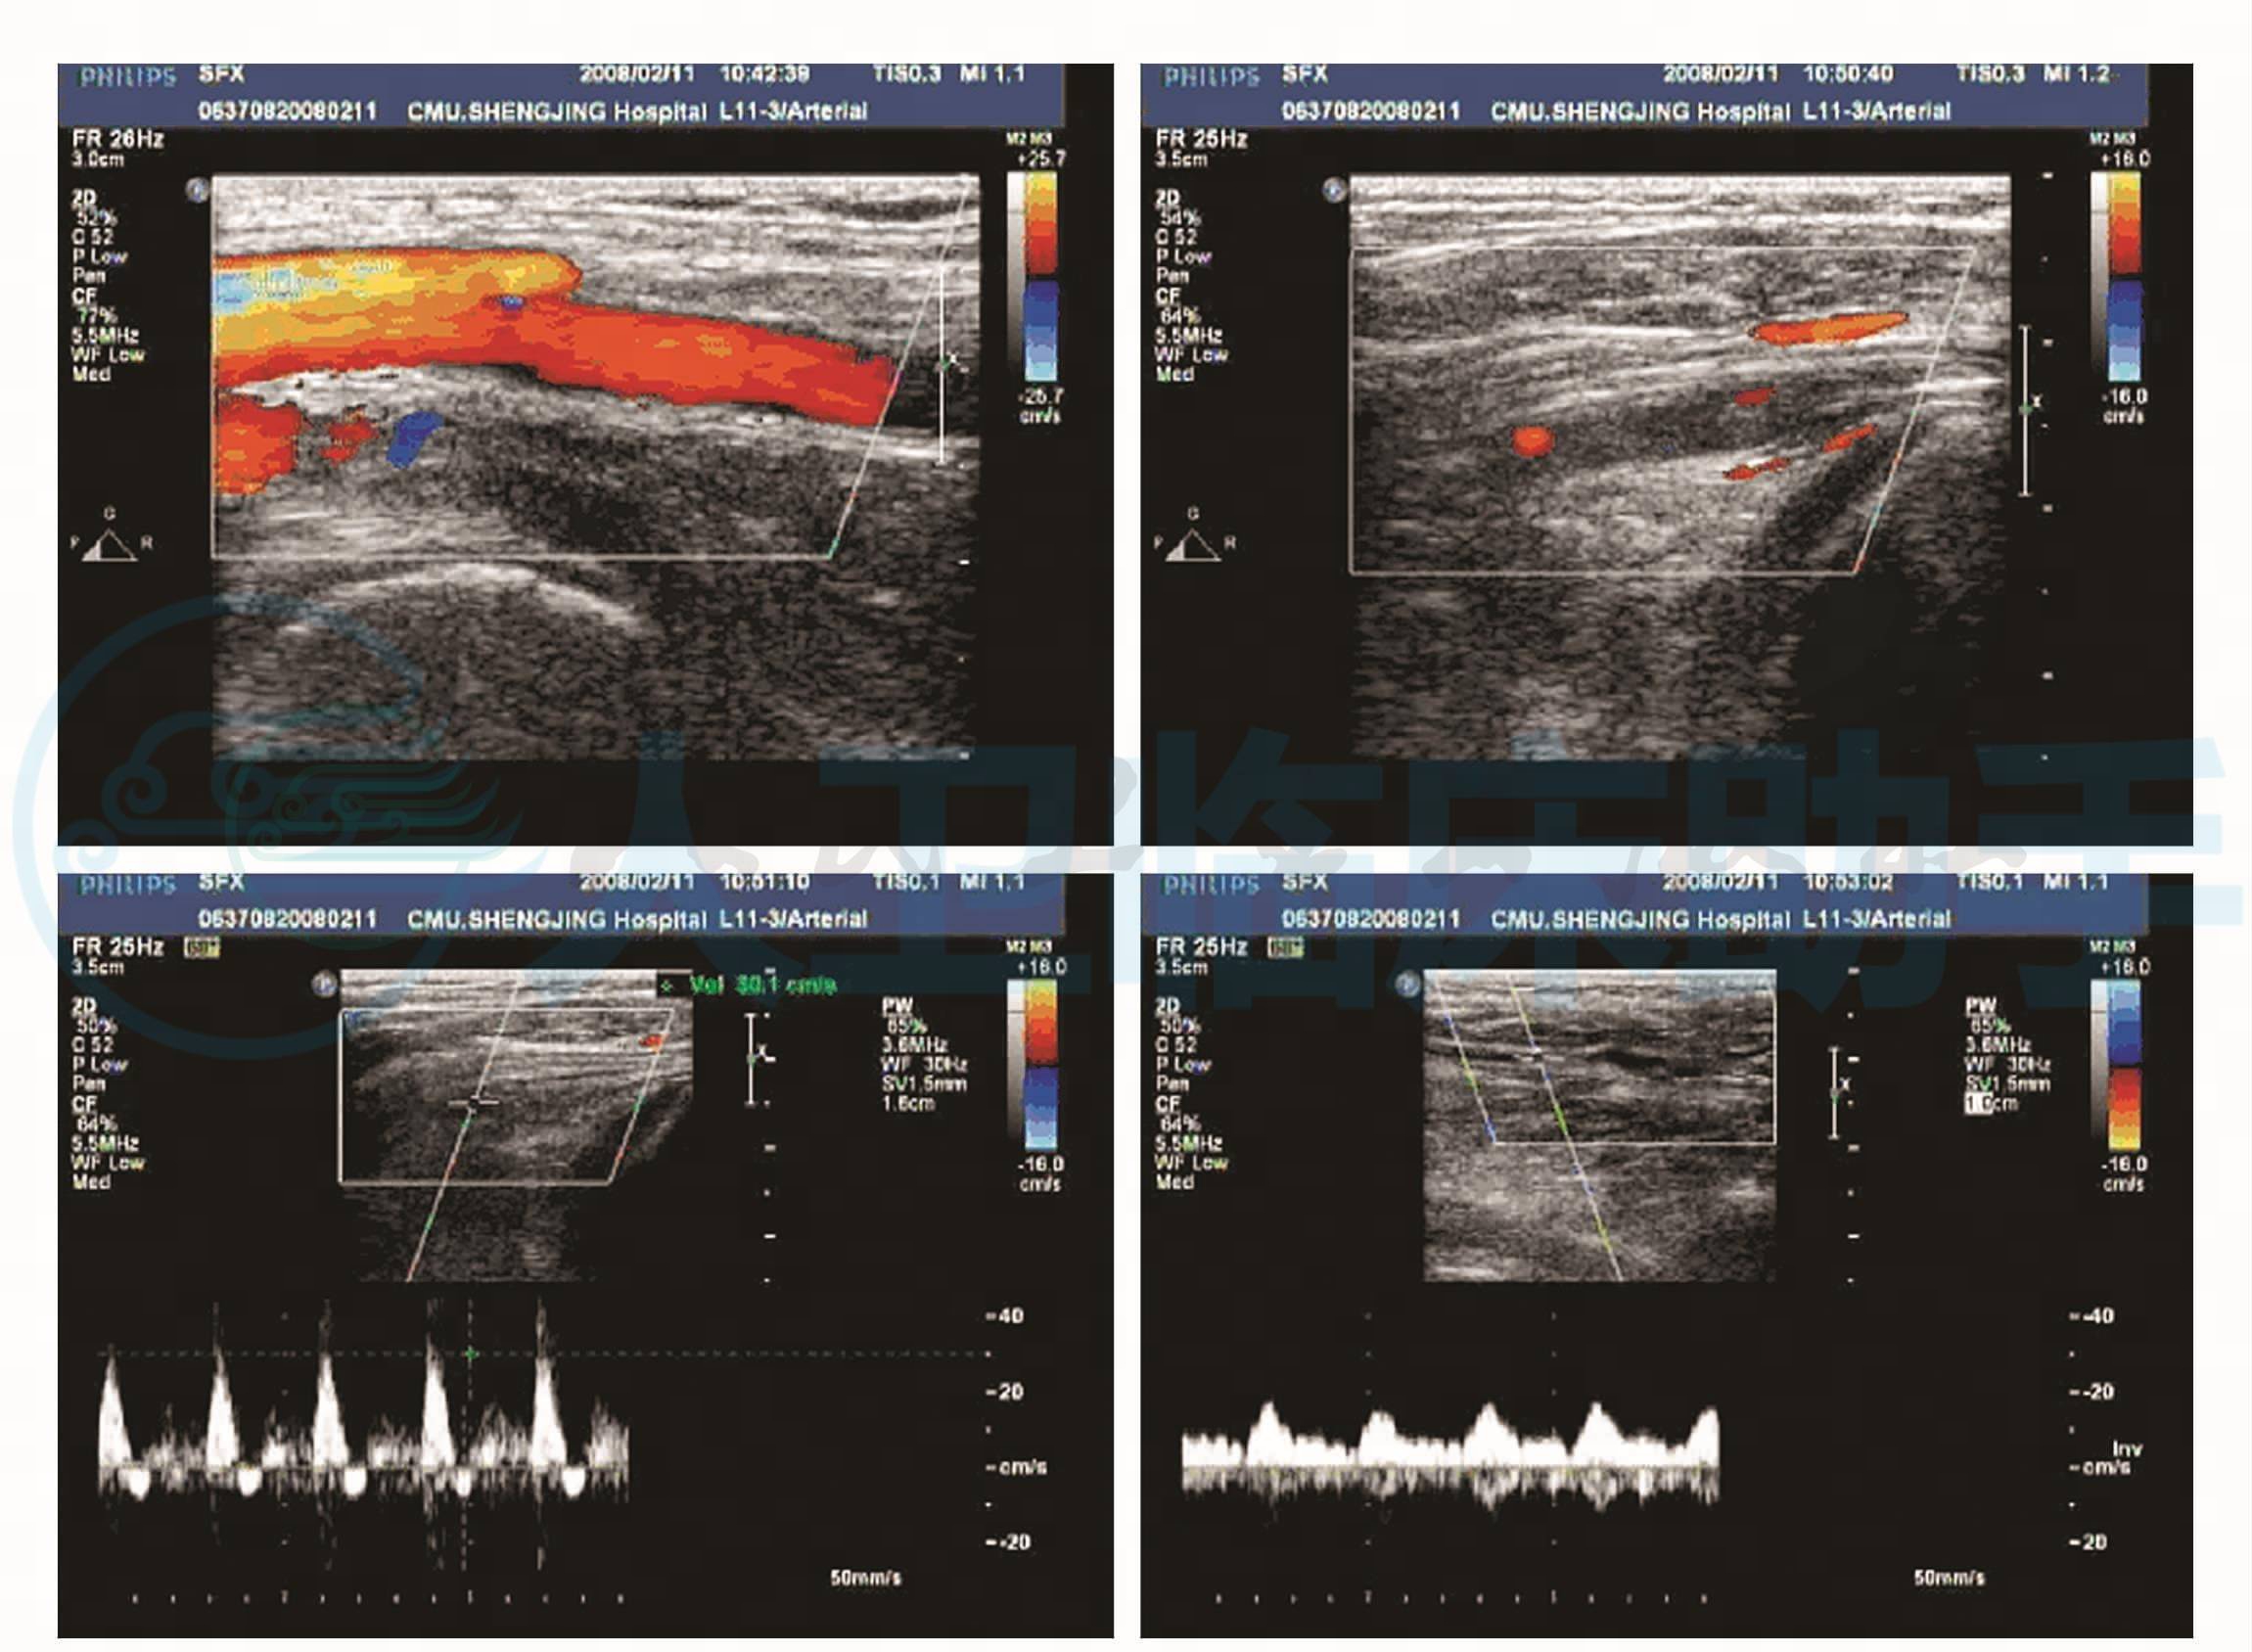

入院第五天(2008年2月11日)患者左下肢胀痛,皮温凉,足背动脉搏动减弱;血管超声显示:左侧腘动脉管腔内可见许多低回声反射,其内少见血流信号,提示左下肢腘动脉血栓形成(图4)。给予尿激酶溶栓。

图4 血管超声示:左下肢腘动脉血栓形成